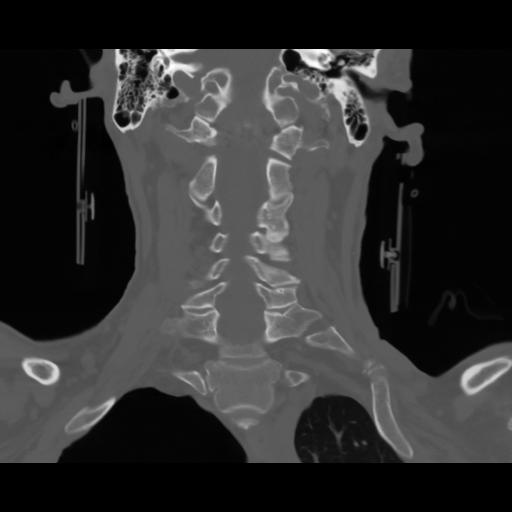

13 P.BLANDAS,,Coronal,2.000,P.BLANDAS,Coronal,